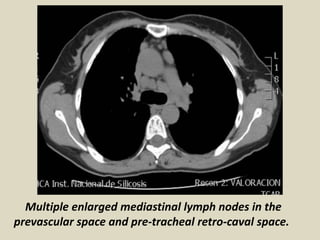

Multiple enlarged mediastinal lymph nodes in the

prevascular space and pre-tracheal retro-caval space.